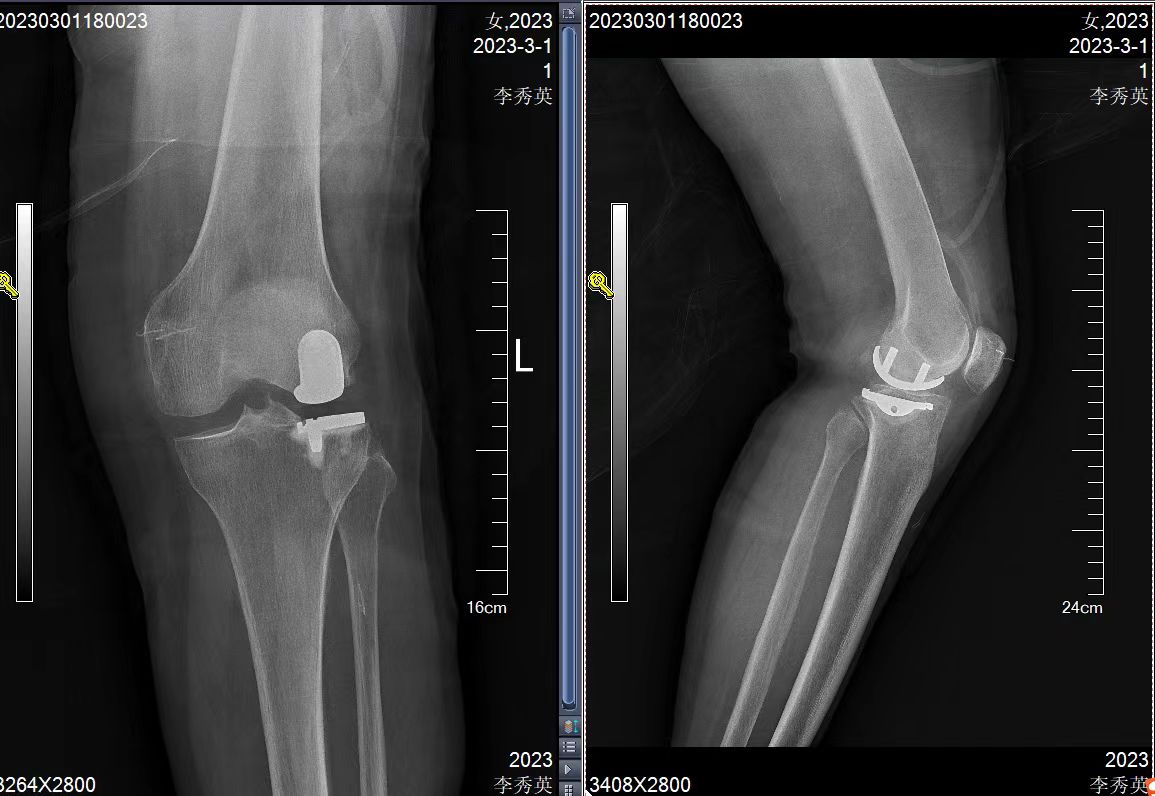

得知西安交通大学第二附属医院王伟教授在洛阳中心医院骨科长期驻科工作后,她抱着试一试的心态来到洛阳市中心医院骨科。王伟教授分析了她的病情:左膝外侧半月板磨损坏了,膝关节外翻变形,而关节其他部分还功能良好,完全可以采用微创保膝手术,保留自己膝关节的大部分。骨科团队给她量身订制了手术方案:外侧单髁关节置换术。家属也联系了北京著名医院的大专家,完全认可手术方案。王伟教授用国际先进的专业术前规划软件,提前进行术前设计,精准预判关节假体大小和安装位置,最终手术仅需7厘米的切口,单髁置换,保膝治疗,取得了康复复周期短,功能恢复好的效果。术后洛阳中心医院骨科王伟民主任、郭哲医师经过数月的耐心随访,解决患者康复中的问题,患者完全恢复了正常生活。精准医疗,量身定制,不仅为患者解决了病痛,而且不必千里迢迢,辗转北京求医。